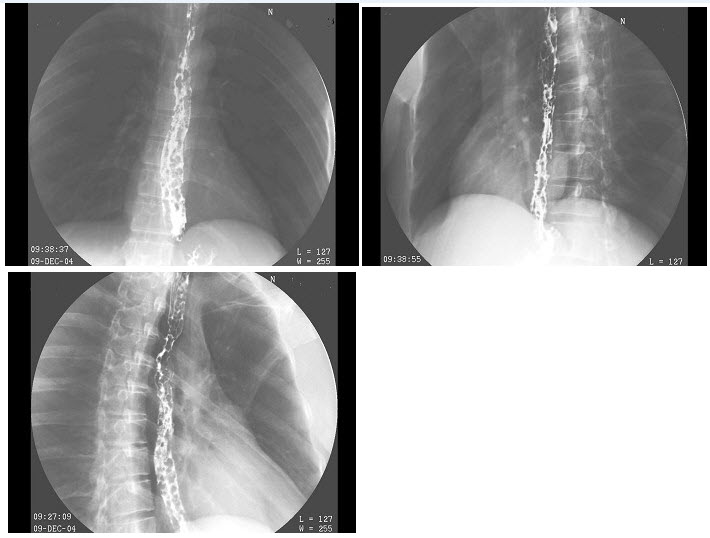

5、单项选择题

男,40岁,黑便1周,半年来呕血两次。查体:脾肋下4cm,结合图像,最可能的诊断为()

A.正常食管

B.食管癌

C.食管静脉曲张

D.贲门癌

E.食管炎

点击查看答案